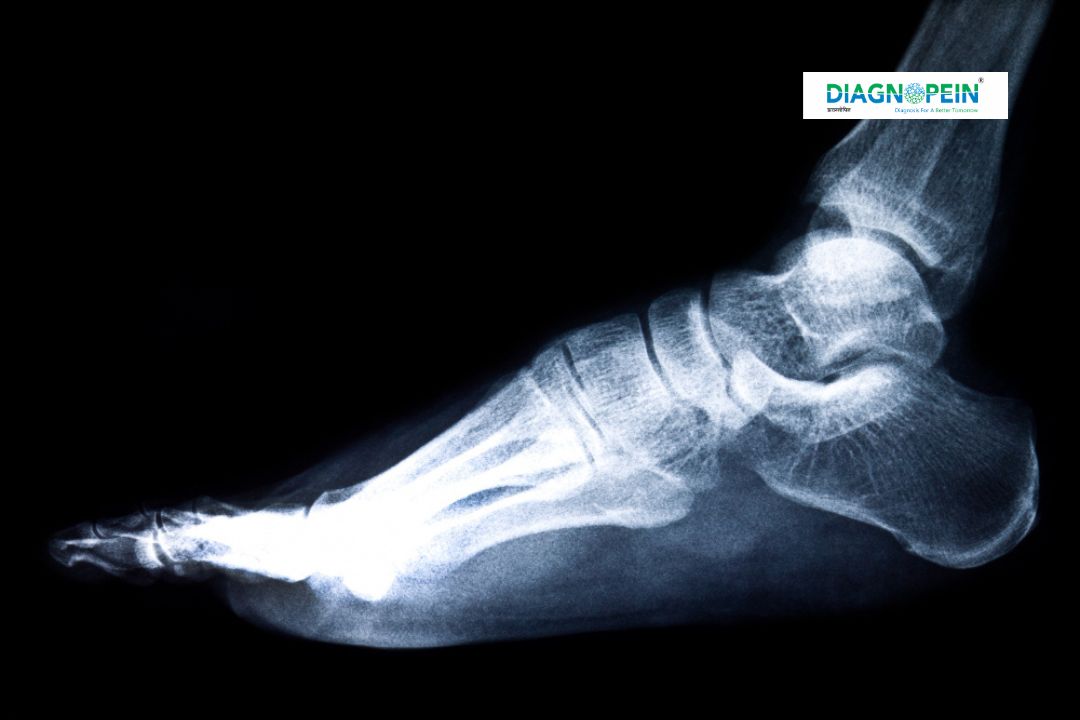

At Diagnopein Karad, the X-Ray Right Foot AP/LAT test is an advanced diagnostic imaging scan used to examine bones, joints, and soft tissues of the right foot. The AP (Anteroposterior) and LAT (Lateral) views provide complementary angles that help healthcare professionals identify fractures, dislocations, bone degeneration, or deformities accurately.

Using digital X-ray technology, our radiologists capture high-resolution images that enable quick and reliable assessments of foot injuries or chronic pain conditions. Whether caused by trauma, sports injury, or medical disorders like arthritis or infection, an X-Ray Right Foot AP/LAT helps pinpoint the root cause effectively.

By analyzing both AP and lateral images, the radiologist can examine the bones in depth—from the heel bone to the toes—ensuring an accurate understanding of the foot’s structure.